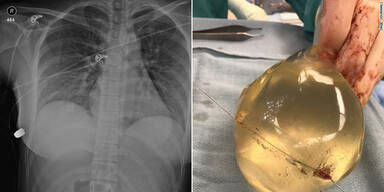

Eine Frau in Kanada hat einen Schuss in ihren Oberkörper nach Einschätzung von Ärzten wahrscheinlich auch dank ihrer Brustimplantate überlebt. Die Richtung der Kugel sei nach dem Aufprall auf eines der Silikonimplantate verändert worden und habe dadurch keine lebenswichtigen Organe getroffen, heißt es in einem Artikel des US-Medizinjournals "SAGE Medical Journal", wie CNN am Dienstag berichtete.

So sei die Einschusswunde an der linken Brust gewesen, die Kugel aber mittels Röntgenaufnahmen unterhalb der rechten Brust geortet und entfernt worden. Ärzte untersuchten diesen Vorfall aus dem Jahr 2018 als Fallbeispiel, wie CNN weiter berichtet. Wer damals auf die Frau in der kanadischen Großstadt Toronto aus naher Entfernung geschossen hat und warum, ist demnach nach wie vor ungeklärt. Die 30-Jährige sei nach dem Vorfall in eine Notambulanz gegangen - Ärzte hätten sich gewundert, in welch guter Verfassung sie sich trotz des Einschusses befunden habe, sagte Giancarlo McEvenue, einer der behandelnden Chirurgen, CNN zufolge.

Die Frau hatte demnach eine Einschusswunde auf der linken Brustseite, einen Rippenbruch auf der rechten Seite und kaputte Implantate, war aber ansonsten bemerkenswert unversehrt. "Die Kugel drang zuerst links durch die Haut, prallte dann über ihr Brustbein in die rechte Brust ab und brach ihr die Rippe auf der rechten Seite. Das Implantat hat die Flugbahn des Geschosses verändert", erklärte McEvenue. Der Fall ist dem Mediziner zufolge einer der wenigen bekannten in der Literatur, in dem ein Brustimplantat eine Rolle bei der Rettung eines Menschenlebens spiele.